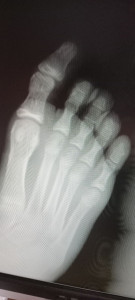

ребенок 13 лет получил травму. Большой палец припух и появилась синюшность. На утро синяки стали коричневого цвета. Припухлость не прошла. Боль соответственно тоже. Сделали снимок. Специалист в рентгенкабинете (не травматолог) сказала, что как минимум трещина, как максимум - перелом. Очень пожилой травматолог сказал, что это всего лишь ушиб. Хотелось бы понять реальную картину и оказать помощь правильно

Здравствуйте. По этим снимкам точно сказать нельзя т.к  качество низкое и без очного осмотра выводы неточные. Но по описанию (отёк, синюшность, боль, сохранение симптомов) трещина или перелом более вероятны, чем просто ушиб. Рекомендую очно показать ребёнка травматологу, повторить снимок в двух проекциях и до уточнения диагноза зафиксировать палец и ограничить нагрузку.

Здравствуйте. По предоставленным снимкам определить перелом однозначно невозможно, но симптоматика настораживает. Припухлость и стойкая боль после травмы в 13 лет чаще сопровождают повреждение кости, чем простой ушиб. Лучше повторить рентген в качественных проекциях и временно обездвижить палец шиной или плотной повязкой. Без уточнения диагноза нагружать ногу нельзя.